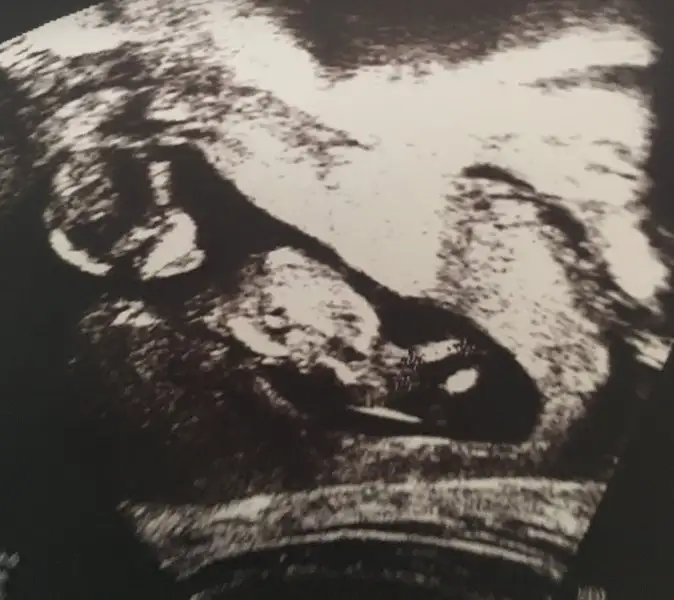

Hcg sonucu var o 50 nin ustu ise kiz dediler benim ustunde mesela bide kalbi 166 o da 140 in ustundeyse kiz dediler o da tutmadi hic bisey tutmadi pipi tuttu

Benim oglanlar koca pipili buyuk oglum 11 haftalik gostermistigördüm valla bende pipiyi hayirlisi ya:)

Maşallah maşallahBenim oglanlar koca pipili buyuk oglum 11 haftalik gostermisti

Valla ben de bacağı ancak anladım pipi falan anlamam hiçanam nasıl anlıyorsunuz nerde pipi